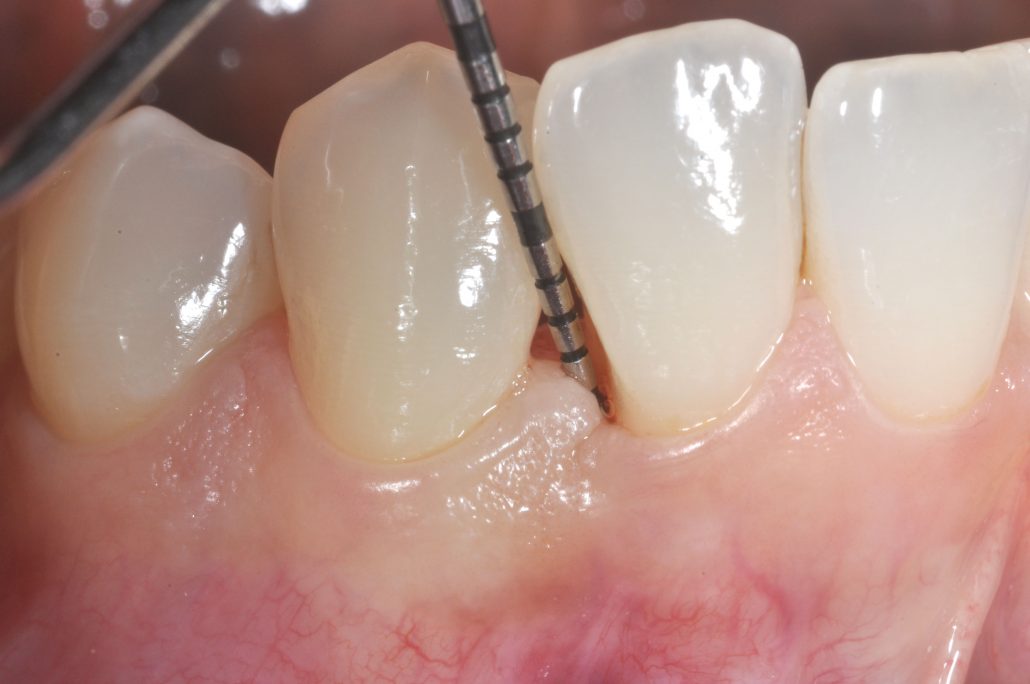

La Parodontologia è quella branca dell’Odontoiatria che si occupa dello studio e della terapia dei tessuti molli e duri che circondano i denti e che ne assicurano la stabilità e il mantenimento funzionale ed estetico. Quando si stabilisce una patologia si parla genericamente di malattie parodontali (piorrea alveolare). In questo caso le gengive sono infiammate, staccate dal dente e sanguinano facilmente.

L’infiammazione può presentarsi in forma più o meno grave. La terapia della malattia parodontale consiste nell’accurata eliminazione dei fattori infiammatori locali quali la placca e il tartaro, nella successiva possibile correzione delle lesioni gengivali ed ossee che la malattia ha provocato e nel mantenimento dei risultati mediante una scrupolosa igiene orale domiciliare e regolari controlli e pulizie periodiche.